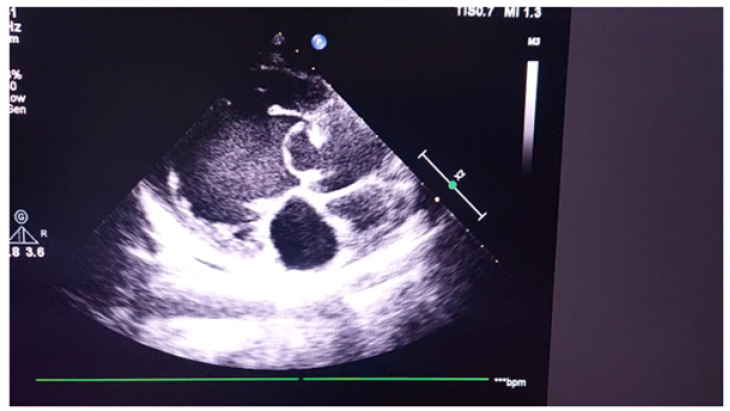

Figure 3 is echocardiogram. It demonstrated a ring-shaped mass attached to aortic valve and its convexity towards left ventricle. Left ventricle was dilated with features of moderate mitral regurgitation and aortic regurgitation. As we did not see the ring-shaped mass attached to aortic valve, we traced the similar photo in internet. It was similar appearance with aneurysm of sinus of Valsalva.

Figure 3a: Echocardiogram demonstrating a ring-shaped mass attached to aortic valve and its convexity towards left ventricle.

Figure 3b: Echocardiogram demonstrating a ring-shaped mass attached to aortic valve and its convexity towards left ventricle.